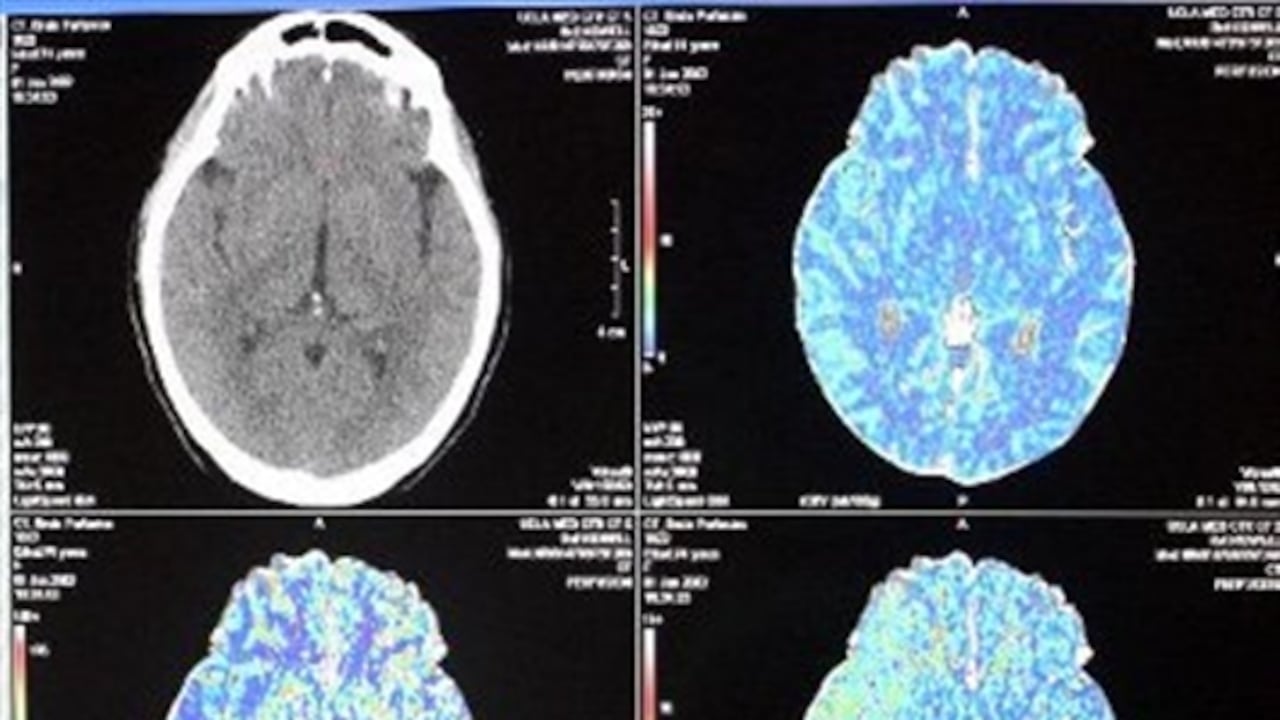

Los científicos examinaron el funcionamiento de las neuronas en dos áreas relacionadas con las percepciones visuales (la corteza parietal y la prefrontal). Entre más cuadrados aparecían en la prueba, mayor era la cantidad de errores.

Lo interesante del ejercicio para Millar fue que “encontramos que los monos, y por extensión los humanos, no tienen una capacidad general del cerebro, por el contrario, tienen dos capacidades distintas en el lado derecho y en el izquierdo. Como si tuvieran dos cerebros separados -los dos hemisferios cerebrales- miraban a diferentes mitades del espacio visual”.